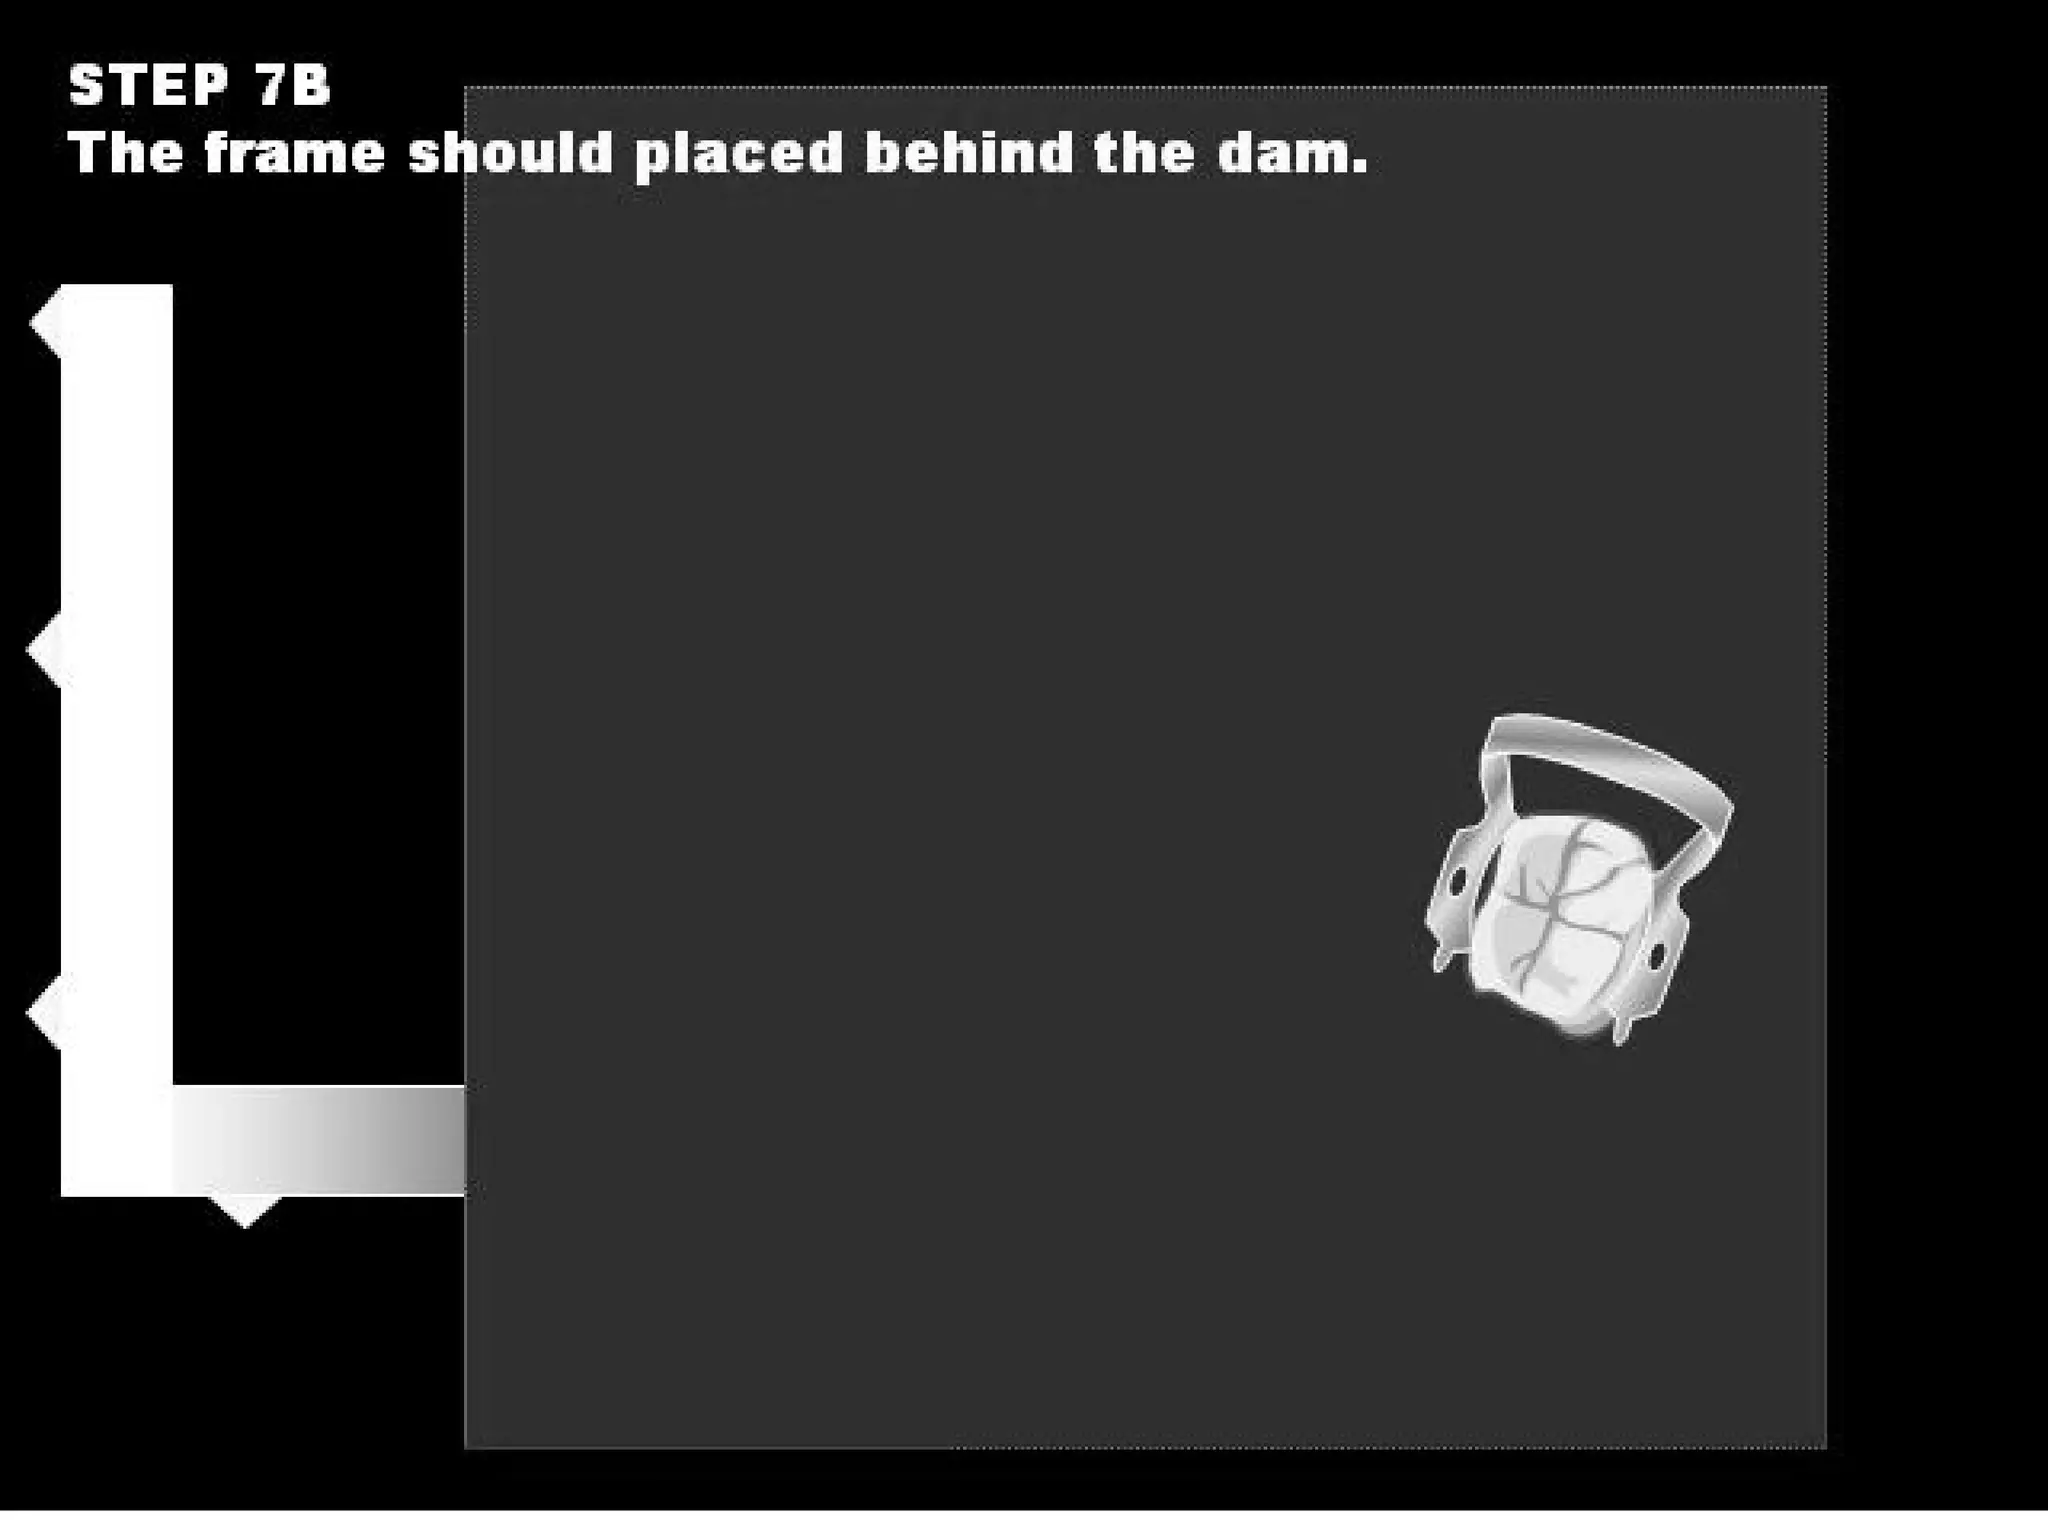

This document discusses the materials and components used for rubber dam isolation in dentistry. It describes the different types of rubber dam materials including color options and napkins to absorb moisture. It also outlines the tools needed such as punches to make holes, templates and stamps to guide hole placement, clamps to secure the dam, and other accessories like wedges and lubricant. Finally, it provides guidance on punching holes for different types of teeth and properly placing clamps in the rubber dam.